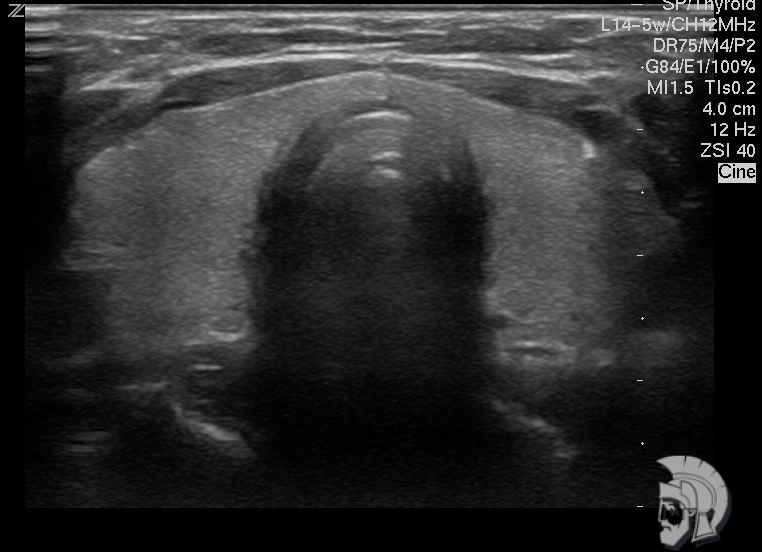

| Фото щитовидной железы. Нормальная щитовидная железа мужчины 35 лет |

Обратите внимание на совершенное качество фотографий, свидетельствующих об экспертном классе аппаратов УЗИ!

Использование ультразвуковых аппаратов экспертного класса с режимами энергетического допплера и цветового допплера позволяет врачам Курортной клиники мужского здоровья выявить патологические изменения щитовидной железы на ранних этапах.